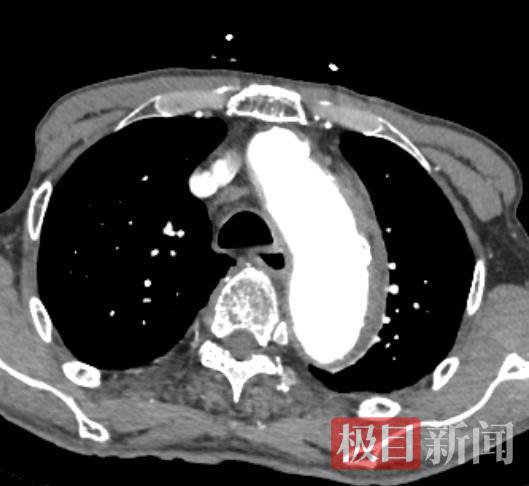

患者主动脉内膜撕裂,形成了一个巨大的血肿

近日,91岁的刘爹爹(化姓)因背部突发拍击样剧痛伴胸闷,被家属紧急送至湖北省中医院(湖北中医药大学附属医院)葛店院区。急诊科医生接诊时发现刘爹爹血压高达220/110mmHg,情况危急,立即联系胸心外科林安忆主治医师会诊。结合症状及初步检查,林安忆高度怀疑是凶险的主动脉夹层,即刻行主动脉CTA检查,确诊为B型主动脉夹层(血肿型)。患者随时面临血管破裂致死的巨大风险,手术刻不容缓。